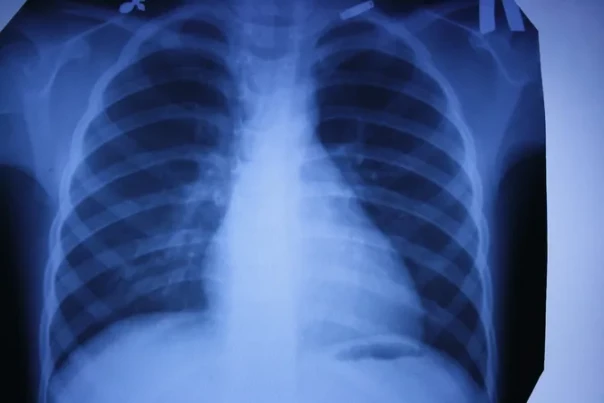

1. Рентген

Рентгеновские снимки — первая в мире диагностическая визуализация. Сложно представить современную больницу без такого обследования. Это и флюорография для проверки наших легких, и снимки при заболеваниях суставов или переломах костей. Обнаружение на ранних стадиях туберкулеза или опухоли в легких увеличивает шансы на выздоровление. Кроме того, жесткое рентгеновское излучение может уничтожать раковые клетки. Принципы современной рентгеноскопии используются и в системах безопасности (сканеры в аэропортах, вокзалах и т. д.), и в производстве. В металлургии или машиностроении равномерность просканированной X-лучами структуры указывает на хорошие прочностные характеристики деталей. Таким же образом проверяются прочность бетонных конструкций для монолитного домостроения, сварные швы сложных металлоконструкций.

Продолжая изучать X-лучи, Рентген получил на своем оборудовании первый снимок костного скелета — кисти руки. С тех пор основные элементы обычного рентгеновского аппарата мало изменились: катодная (рентгеновская) трубка, питающее устройство (два трансформатора) и пленка-фотобумага из соединений серебра с галогенами, которые темнеют с различной интенсивностью в зависимости от плотности просвечиваемого материала и тем самым формируют изображение.

В 1917 году для анализа рентгеновских снимков был применен экспоненциальный закон ослабления излучения в веществах, который показал высокую точность. Это привело к появлению компьютерной томографии (трехмерного рентгена) — послойного исследования тканей и создания изображения с учетом разности поглощения рентгеновского излучения различными по плотности тканями. Изобретатели томографа — американец Аллан Кормак, разработавший в 1963 году математический алгоритм для томографического восстановления изображения, и британец Годфри Хаунсфилдом из фирмы EMI Ltd. Британец, используя алгоритм Кормака, в 1971 году создал первый компьютерный рентгеновский томограф EMI-scanner для сканирования мозга. В 1979 году оба получили Нобелевскую премию за разработку компьютерной томографии. Томограф проводит более точное диагностирование отдельных органов, а в особенности важен для определения заболеваний мозга и сосудов. Многие жизни были спасены благодаря безошибочному определению типа инсульта при помощи компьютерной томографии, которая и до сих пор считается важным условием диагностирования такого заболевания.